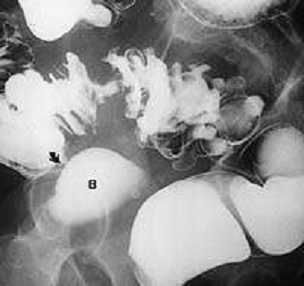

Стадии и особенности дивертикулярной болезни по классификации Hinchey